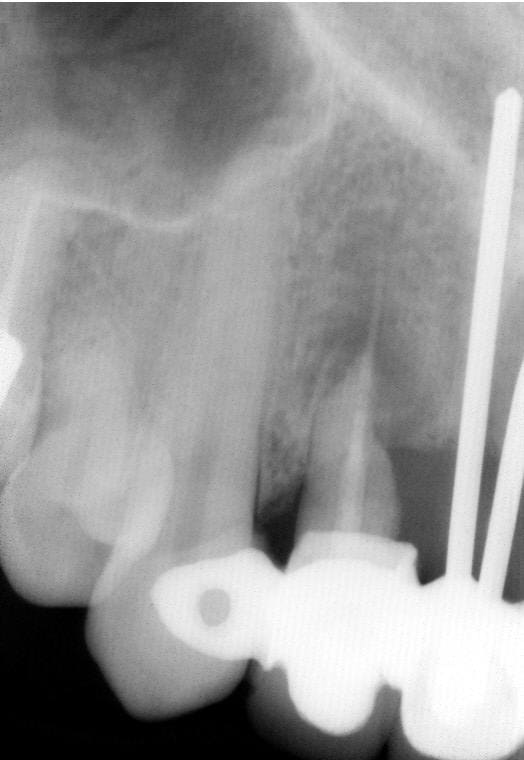

Par exemple :

Photos endopore Et radio d'un calcitek